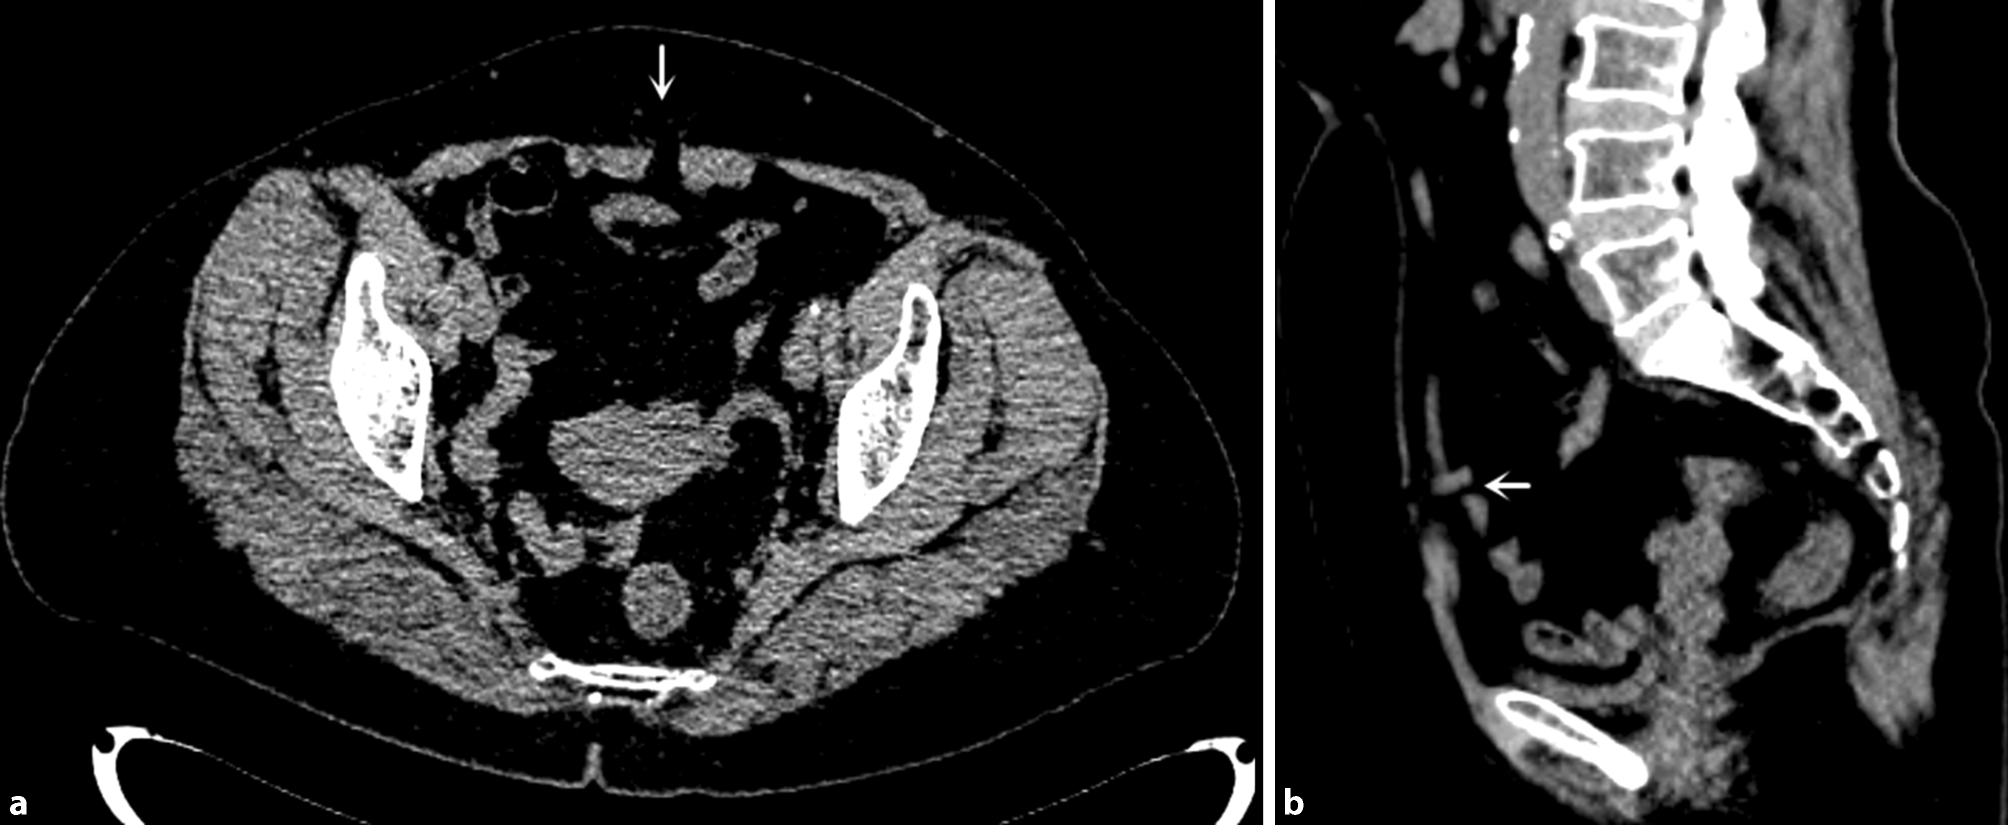

Computed tomography (CT) revealed a local defect (size, 0.7 cm) in the linea alba of the lower abdomen with abdominal fat entering the subcutaneous fat layer through the defect (Fig. 1). Linea alba hernia was confirmed during surgery. There was no hernia sac, only a portion of the median umbilical ligament was embedded into the hernia ring and it was difficult to pull back into the abdominal cavity. We removed this section of the median umbilical ligament and observed a hernia ring (1.0 cm in diameter) in the linea alba. The median umbilical ligament and its accompanying blood vessels traversed the hernia ring (Fig. 2). The linea alba defect and peritoneum were sutured, and the hernia was repaired using the intraperitoneal onlay mesh (IPOM) technique with an intraperitoneal preformed patch.

Fig. 1

Computed tomography images of a local 0.7-cm defect in the linea alba of the lower abdomen and abdominal fat entering the subcutaneous fat layer through the defect (white arrow)